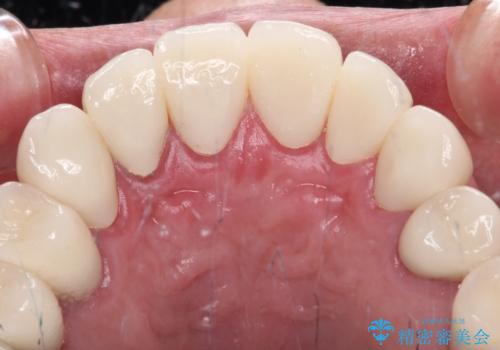

憧れの白い歯に 全顎セラミック治療

- 60歳を越え、黄ばんだ前歯をセラミッククラウンできれいな口元にしたいとのことで来院された患者様です。

診察したところ、前歯は反対咬合であり、その影響で抜歯が必要な奥歯があることが分かりました。

抜歯が必要な奥歯は、インプラント並びにブリッジにより補綴を行い、上下前歯は反対咬合を改善させるように補綴治療を行うこととしました。

健全な歯を削ってセラミッククラウンに置き換えることは、本来避けるべき治療と考えますが、今回は①患者様が60歳を越えていること、②要改善の咬合により抜歯が必要な奥歯があること、③反対咬合の前歯改善の手段としてセラミック治療が選択肢にあることなどから、全顎的なセラミック治療を行うこととしました。